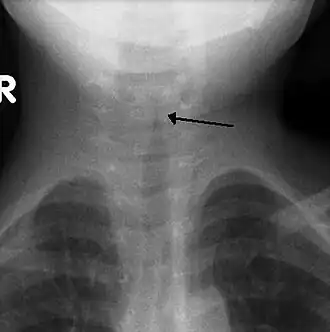

![]() Rentgenový snímek dítěte s krupem | |

Rentgen krku se obvykle neprovádí,[4] je-li ale realizován, může ukázat zúžení průdušnice, anglicky zvané symptom „kostelní věže“, protože tvar zúžení připomíná kostelní věž. Symptom „kostelní věže“ se objevuje jen v polovině případů.[3]